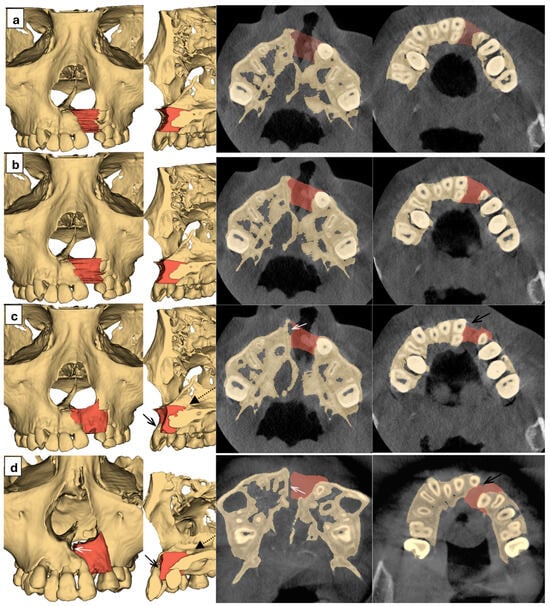

Standardization and Validation of Digital Volumetric Measurement Methods for Alveolar Cleft Defects Using 3D Imaging

Background/Objectives: Accurate quantification of alveolar cleft defects for bone grafting remains difficult due to inconsistent anatomical boundaries. This study established an expert consensus on boundary landmarks for alveolar bone graft (ABG) planning and validated the accuracy and reliability of digital volumetric measurement methods. Methods: Three cleft specialists performed repeated simulated graft procedures in seven patient-specific 3D-printed models, first according to the operator’s clinical judgment, and subsequently according to panel-derived consensus boundaries. Two radiologists independently conducted digital volumetric assessments in 3D X-ray imaging using four measurement approaches (axial tracing, interpolated axial tracing, landmark-based mirroring, and mesh-based mirroring), generating 56 independent digital segmentations to be evaluated against the consensus-based physical reference standard. Volumes of the defects were recorded, intra- and inter-rater reliabilities were calculated using the intraclass correlation coefficient (ICC), and differences among methods were analyzed. Results: Operator-defined plans showed significant inter-operator differences (p < 0.001) with poor-to-excellent reliability (intra-rater ICC 0.060–0.967; inter-rater ICC 0.300–0.635). Consensus established standardized boundaries: tilted plane from base of anterior nasal spine to hard palate, cemento-enamel junctions, incisive canal, and alveolar contour. Consensus-based filling showed non-significant inter-rater differences (p = 0.139) and substantially improved reliability (intra-rater ICC 0.904–0.988; inter-rater ICC 0.622–0.861). Among the four digital methods evaluated, axial tracing demonstrated excellent reliability (intra-rater ICC 0.971–0.99; inter-rater ICC 0.965) and high accuracy (mean difference 0.001–0.026 cm3), with no significant difference (p = 0.999) from the physical reference standard. Conclusions: These proposed consensus-based boundary definitions and validated volumetric measurement methods improved the accuracy and reproducibility of personalized alveolar bone graft planning. Full article